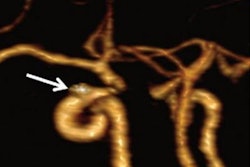

Patients undergoing stent placements to treat brain aneurysms typically receive dual antiplatelet therapy (aspirin and clopidogrel) to thin their blood prior to procedures. This reduces the formation of blood clots after procedures, which can lead to strokes, the authors explained.

Thus, in a prospective trial in 590 participants (median age, 58 years old), the researchers tested whether one such test, a light transmission aggregometry test (AG800, Techlink Biomedical Technology), could reduce strokes in patients after stent placements. The trial involved sixteen treatment teams from eight public hospitals across three cities between May and August 2023.